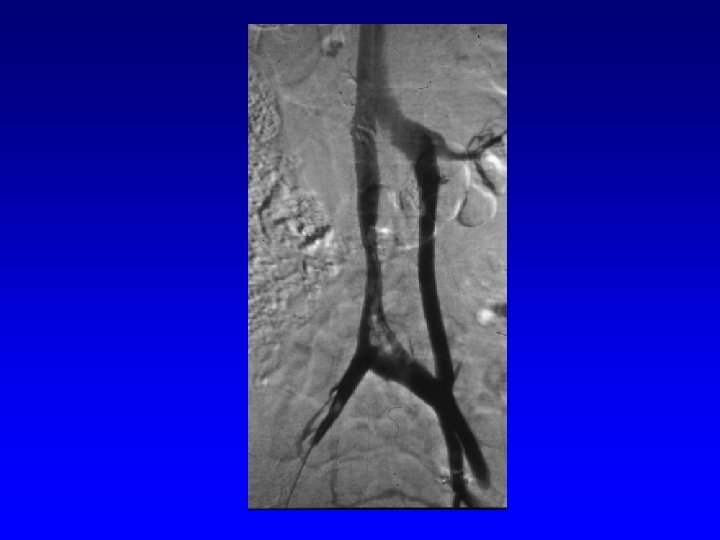

Classic Filter Indications Thrombo-embolic disease (TED) with Contraindication for anticoagulation. Complication of anticoagulation. Failure of anticoagulation. Massive pulmonary embolism. Chronic, recurrent pulmonary embolism.

Extended Indications - Off Label DVT/PE with poor compliance. “Widow maker” thrombus. Poor respiratory/pulmonary reserve. Unsteady patient (fall risk). No DVT/PE but at high risk for development.